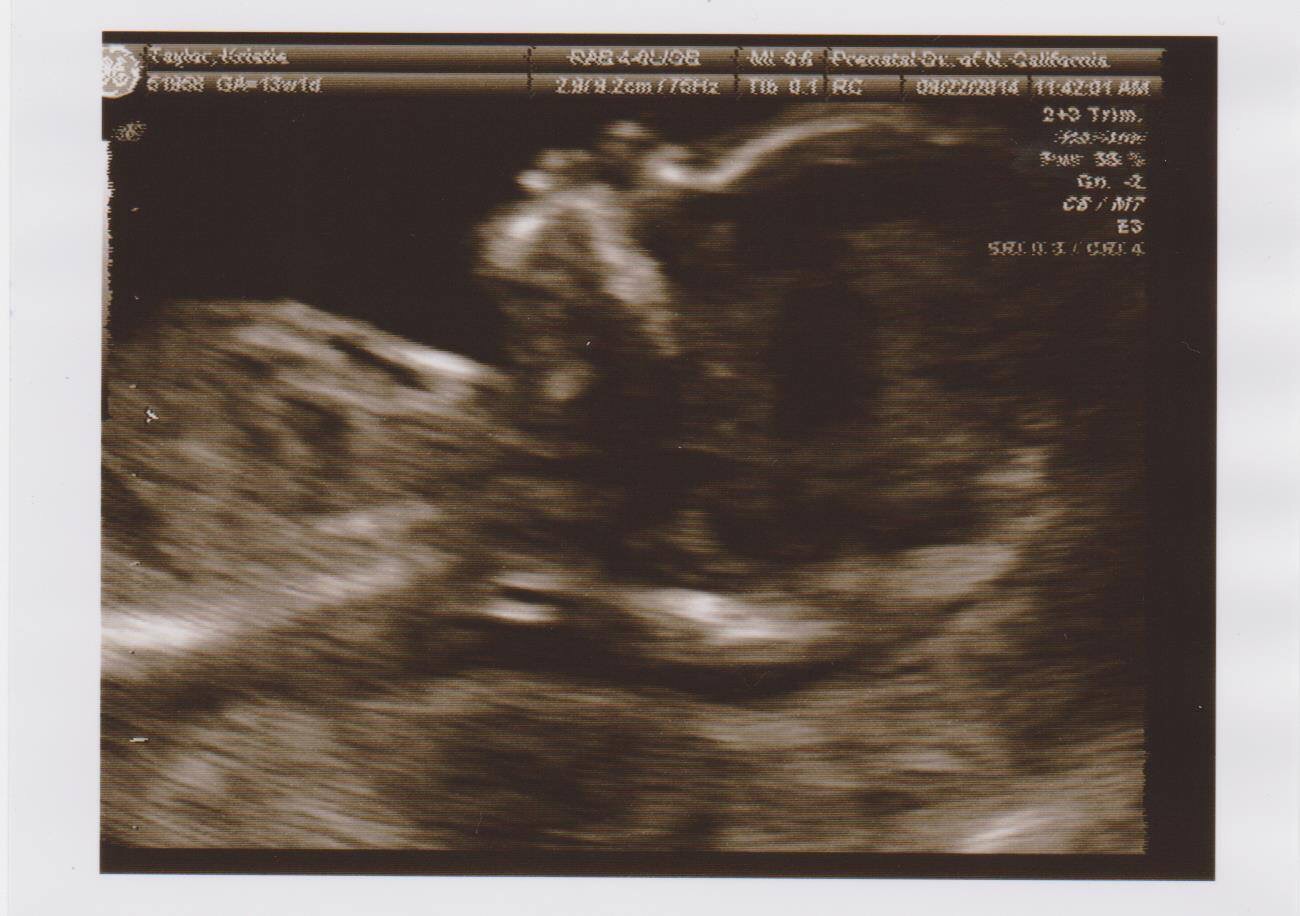

• Had mine yesterday!!! LO was not very cooperative at first, but eventually flipped onto the side and we got a great profile of the nose! Fluid measured between 1.4-1.5 which was great. Won't get my blood results back till next week but I am feeling good! @Anne1387‌ I wasn't told anything about water either, when I got there the tech wouldn't let me use the bathroom though. I think it has something to do with trying to push the baby into position? My tech was rough! Baby did not like her. We could see its little mouth opening and shutting and she said baby was laughing at her....but I think baby was yelling/crying :( The doctor was much more gentle and baby listened to him.